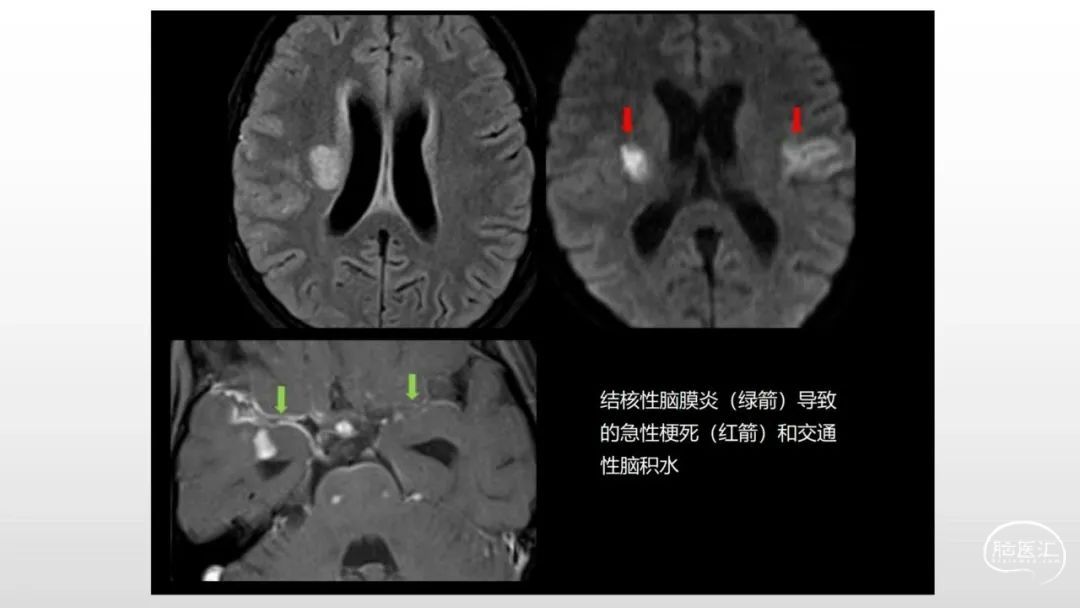

颅脑影像诊断基础知识讲座:感染和免疫性疾病2